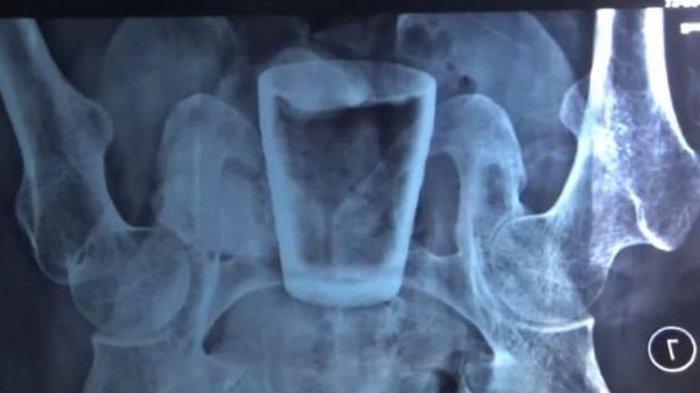

Tribunjogja.com - Aneh tapi nyata. Sebuah gelas kaca berhasil dikeluarkan tim medis di RSD Balung Jember dari perut seorang pasien.

Berdasarkan pemeriksaan medis, terdapat gelas di perut pria tersebut. Sehingga, pria itu harus menjalani operasi di rumah sakit.

Humas RSD Balung dr Doddy Radhi Sakti menjelaskan, pasien tersebut mendatangi rumah sakit pada 28 Maret 2022. Kemudian, pihak rumah sakit melakukan rontgen.

“Kami foto rontgen dulu, ternyata ditemukan bentukan berupa gelas,” kata Doddy kepada Kompas.com via telepon, Rabu (6/3/2022).

“Dari pasien tidak ada pengakuan dari mana masuknya gelas itu,” kata dia. Tim medis melakukan operasi untuk mengelarkan gelas itu pada 29 Maret 2022. Posisi gelas itu terdapat di bagian rectum atau anus. Gelas itu berhasil dikeluarkan setelah melewati proses operasi yang berlangsung sekitar dua jam.

“Di dalam rektum itu tidak terdapat pecahan kaca,” tambah dia.